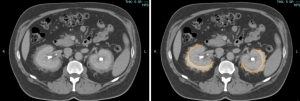

MULTIDETECTOR COMPUTED TOMOGRAPHY (MDCT)

RPF typically appears as a well-defined, irregular paraspinal soft-tissue mass, isodense to the psoas muscle and without lateral extension beyond it. Most often centred at L4–L5 near the aortic bifurcation, it may extend cranially towards the renal hila or, less commonly, caudally to involve pelvic structures. Baseline Hounsfield units (HU) values and the diameter of the retroperitoneal tissue can assist in assessing inflammatory activity. [1,3,5-8]